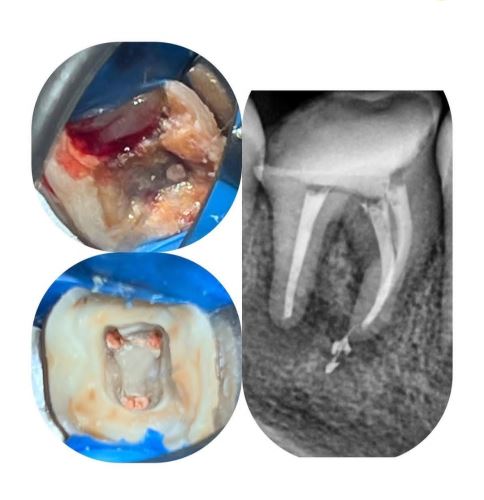

درمان ریشه ( عصب کشی) پیشرفته

درمان ریشه (Root Canal Therapy)

یک روش دندانپزشکی برای نجات دندانی است که پالپ (عصب و بافت داخلی) آن عفونی یا آسیبدیده شده. این درمان شامل مراحل زیر است:

3. پاکسازی کانالها: خارج کردن پالپ عفونی و تمیز کردن کانالهای ریشه.

4. پر کردن کانال: با مواد مخصوص (مثل گوتا پرکا) برای جلوگیری از عفونت مجدد.